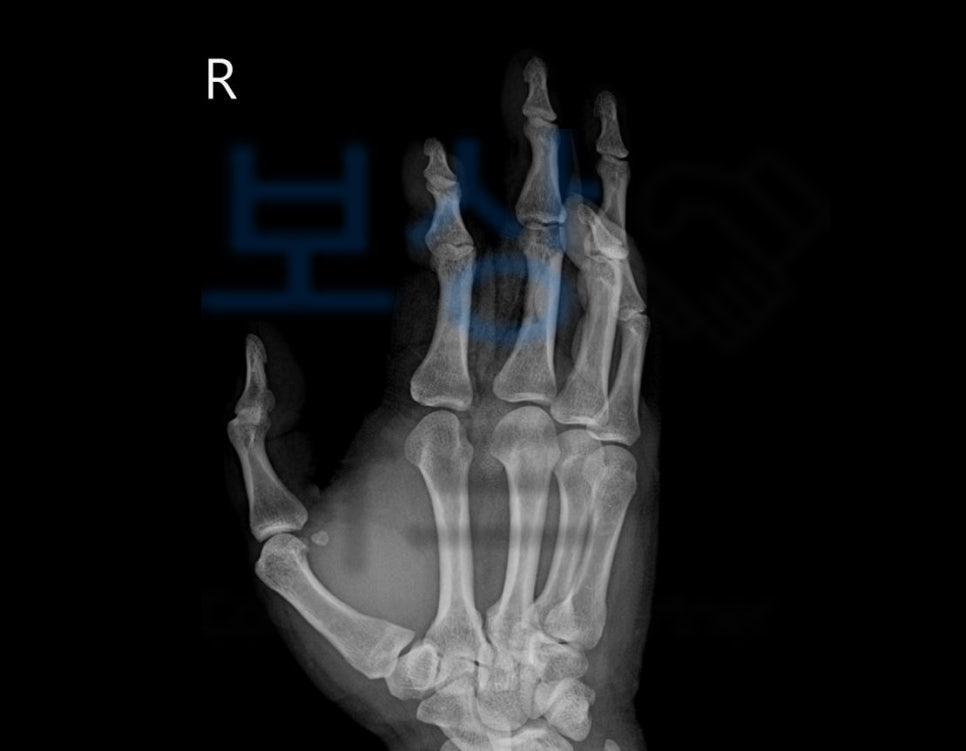

송@@님은 회사에서 일하시다가 프로펠러에 손이 들어가버리는 사고를 당하셨습니다.

위 사고로 고객님은

2수지 개방성 골절 s62631

3수지 굴곡건 파열 s6610

및 2-4수지 피부 결손, 괴사 등의 진단을 받아

골절된 뼈를 맞추는 금속 고정술, 굴곡건 파열 의 건봉합술 등등 수술적 치료가 불가피했죠. 골절진단비 나 실비, 입원비는 보험사에서 요청하는 진단서, 영수증만 청구해도